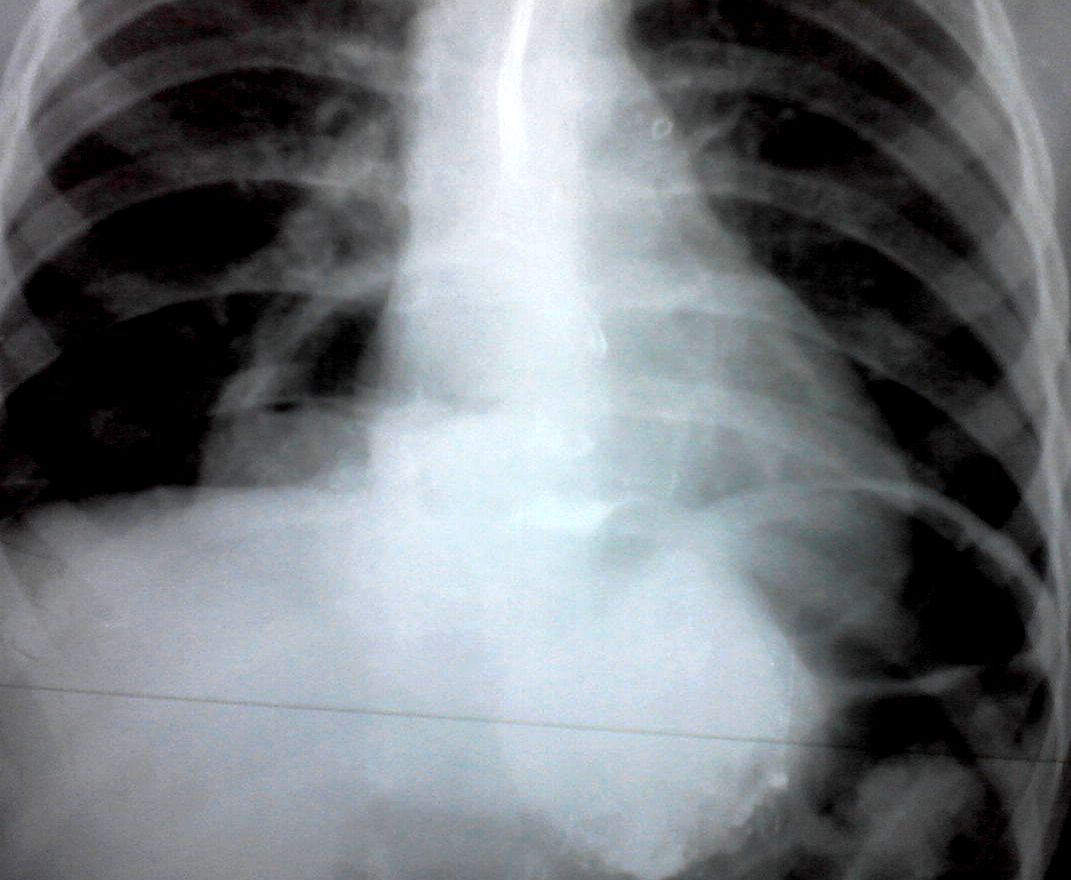

Образование в средостении - диафрагмальная грыжа

Девочка 4-х лет, жалобы на длительный кашель (оеоло 1-го месяца). В поликлинике выполнена рентгенография органов грудной клетки, выявлены изменения (какие - пока не скажу). Госпитализирована. Направлена на УЗИ сердца. При УЗИ - в самом сердце - патологии не выявлено, но позади него к правому предсердию прилежит полостное образование с акустически неоднородным содержимым.